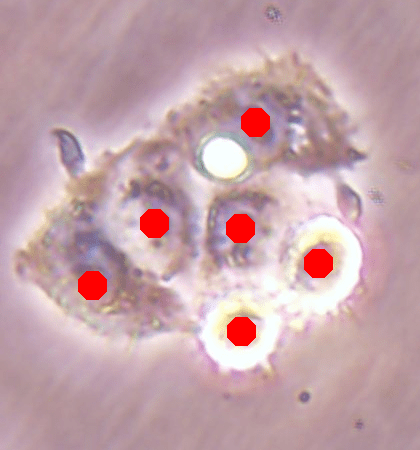

Before the advances in deep learning, the traditional approach for cell detection/segmentation is to employ low-level handcrafted features, reflecting color, edge, and shape characteristics of cells. This approach has given promising results when the features are defined properly, as a good representation of the visual cell characteristics. On the other hand, these characteristics may change from one cell type to another (see Fig. 1) and new features need to be defined to meet the cell characteristics of a new type. Additionally, when there exists heterogeneity in the visual characteristics of the same cell type, using a single model may not be sufficient to detect all cells of this type, particularly for cancer cells which are exploited more in high throughput screening.

![]() |

| (a) | (b) | (c) |

We test our DeepDistance model on three datasets, each of which consists of live cell images of a different cell line. They are the CAMA-1, MDA-MB-453, and MDA-MB-468 human breast cancer cell lines. The images in all datasets were acquired at magnification and pixel resolution. An example image from each dataset is shown in Fig. 1. As seen in this figure, cells might be visually different within and across different cell lines.